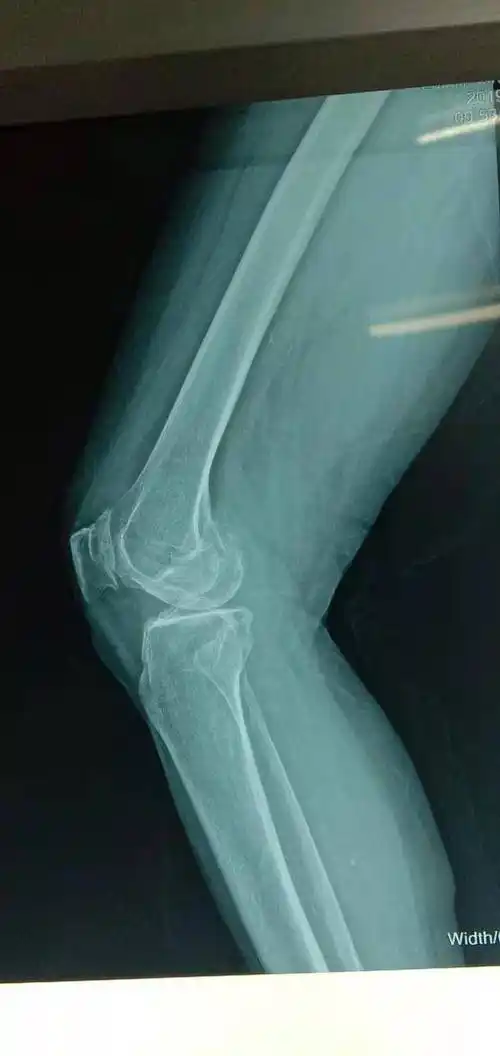

三院骨科积极创新,关节置换快速康复